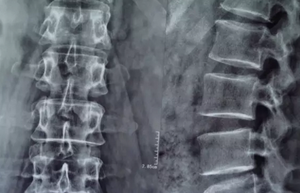

来到我院后,对蒋先生进行了检查,诊断为“腰椎间盘突出症(腰4/5、腰5/骶1),腰椎管狭窄症,腰椎退行性病,颈椎间盘突出症颈(3/4、颈4/5、颈5/6、颈6/7)”。8月3日,经过麻醉后,由胡玉华院长,李龙付副主任为其做了“腰4/5、腰5骶1椎间盘摘除+腰4、5全椎板切除减压融合钉棒内固定术”手术。两个半小时的手术顺利完成了。